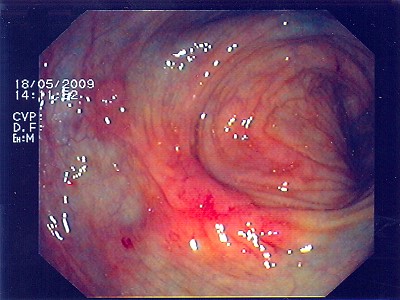

Polypabtragungsstelle